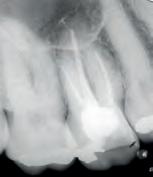

We recommend the following steps for professional whitening evaluation and treatment.

Evaluate the origin of tooth staining and check for restorations that could affect the final result (use X-Ray if needed). Assess the intention of whitening system (cosmetic for generic “day-by-day” discoloration; medical devices for teeth discolored by disease, injury or medical treatment). Consider amending your periodical medical history by adding a question about the patient’s satisfaction with their oral esthetics. Explain to the patient that restorations will not whiten, and discuss the possible need for new restorations after whitening. Check existing sensitivities, and perform an adequate treatment before starting a whitening procedure. Pregnant or breastfeeding women should not whiten. Patients with serious health concerns should consult their primary care provider prior to treatment. Cosmetic teeth whitening treatments are not permited under the age of 18.